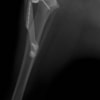

術前左後肢側面像

術後左後肢側面像

手術前後のTPA(脛骨高平部の角度)を測定しています。

約29°から約10°へ矯正されています。

本症例は、走った後に左後肢を挙上していることを主訴に来院されました。触診時に左膝関節のクリック音を聴取、レントゲン検査にて左脛骨の前方変位が認められました。術中に、前十字靱帯の断裂及び内側半月板の損傷、内側の軟部組織の顕著な腫脹を確認。半月板切除、TPLOを実施しました。周囲組織への炎症の波及もあったため回復に時間を要しておりますが、徐々に跛行頻度は減少傾向にあり、現在も経過観察中です。術前に約29°あったTPAは術後に約10°まで矯正されました。